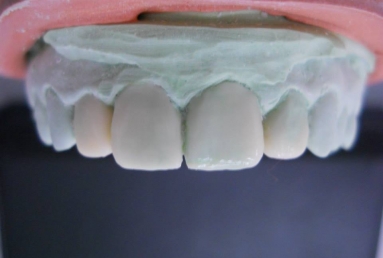

Very small lateral incisors covered with full ceramic crowns and ceramic veneers on central incisors. The prosthetic space was correctly split between the four incisors, in order to reduce the disproportion between the large centrals and the very small laterals. The preparation of the teeth was minimally invasive, all four incisors remained vital.